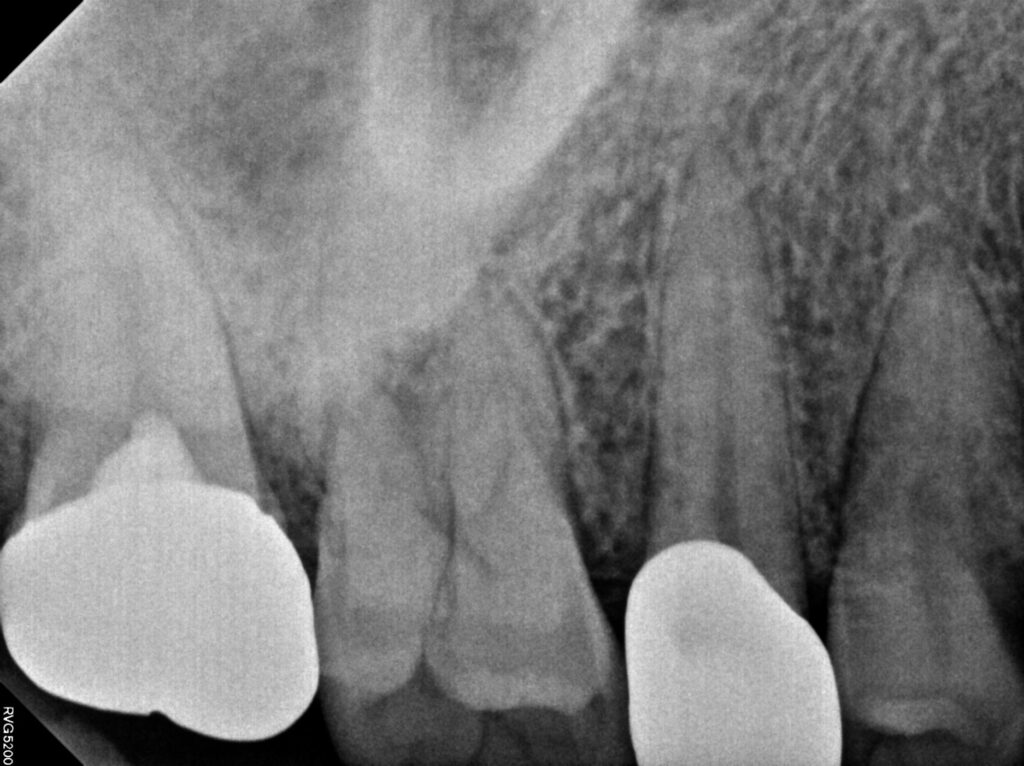

환자분께서는 치아에 금이 뿌리까지 이어져

치근 파절로 진단 되어 이런 경우에는 신경치료를

진행한다고 해도 예후가 좋지 않아

빠르게 발치 후 임플란트를 진행하는 것이

낫다고 판단되어 진행하시기로 하였습니다.

치아에 균열이 생긴 경우

깊이와 범위에 따라 달라지는데

비교적 얕은 크랙은 손상 부위를 정리한 뒤

레진으로 충전해 기능을 회복할 수 있습니다.

균열이 더 진행된 경우에는 인레이나 온레이와 같은

보철물을 통해 치아 구조를 보강하는

방식이 적용되며 신경까지 손상이 진행됐다면

근관치료 후 크라운을 씌워 치아를 보호하게 됩니다.

균열이 치근까지 깊게 진행되거나

이미 파절이 발생한 경우에는 자연치 보존이 어려워

발치 후 임플란트 치료가 불가피 하므로